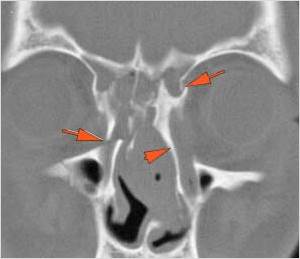

21-year-old male in the emergency room following an altercation with possible orbital or other facial fractures.Exam

There is evidence of herniated intra-orbital fat. |

Yes | NA |

The extraocular muscles are swollen, infiltrated or herniated into a fracture site. |

There is evidence of bony injury along the walls and/or floor of the orbit. |

The mesial naso-orbito-ethmoid complex is fractured. Specifically, there is bony injury of the nasal bones or the frontal process of the maxilla and the medial walls of the orbit are abnormal. |

Orbital floor fracture on the left with significant entrapment of orbital fat and entrapment of the inferior rectus muscle in a likely trapdoor type mechanism and minimally displaced fractures of the medial orbital wall and nasal bones.